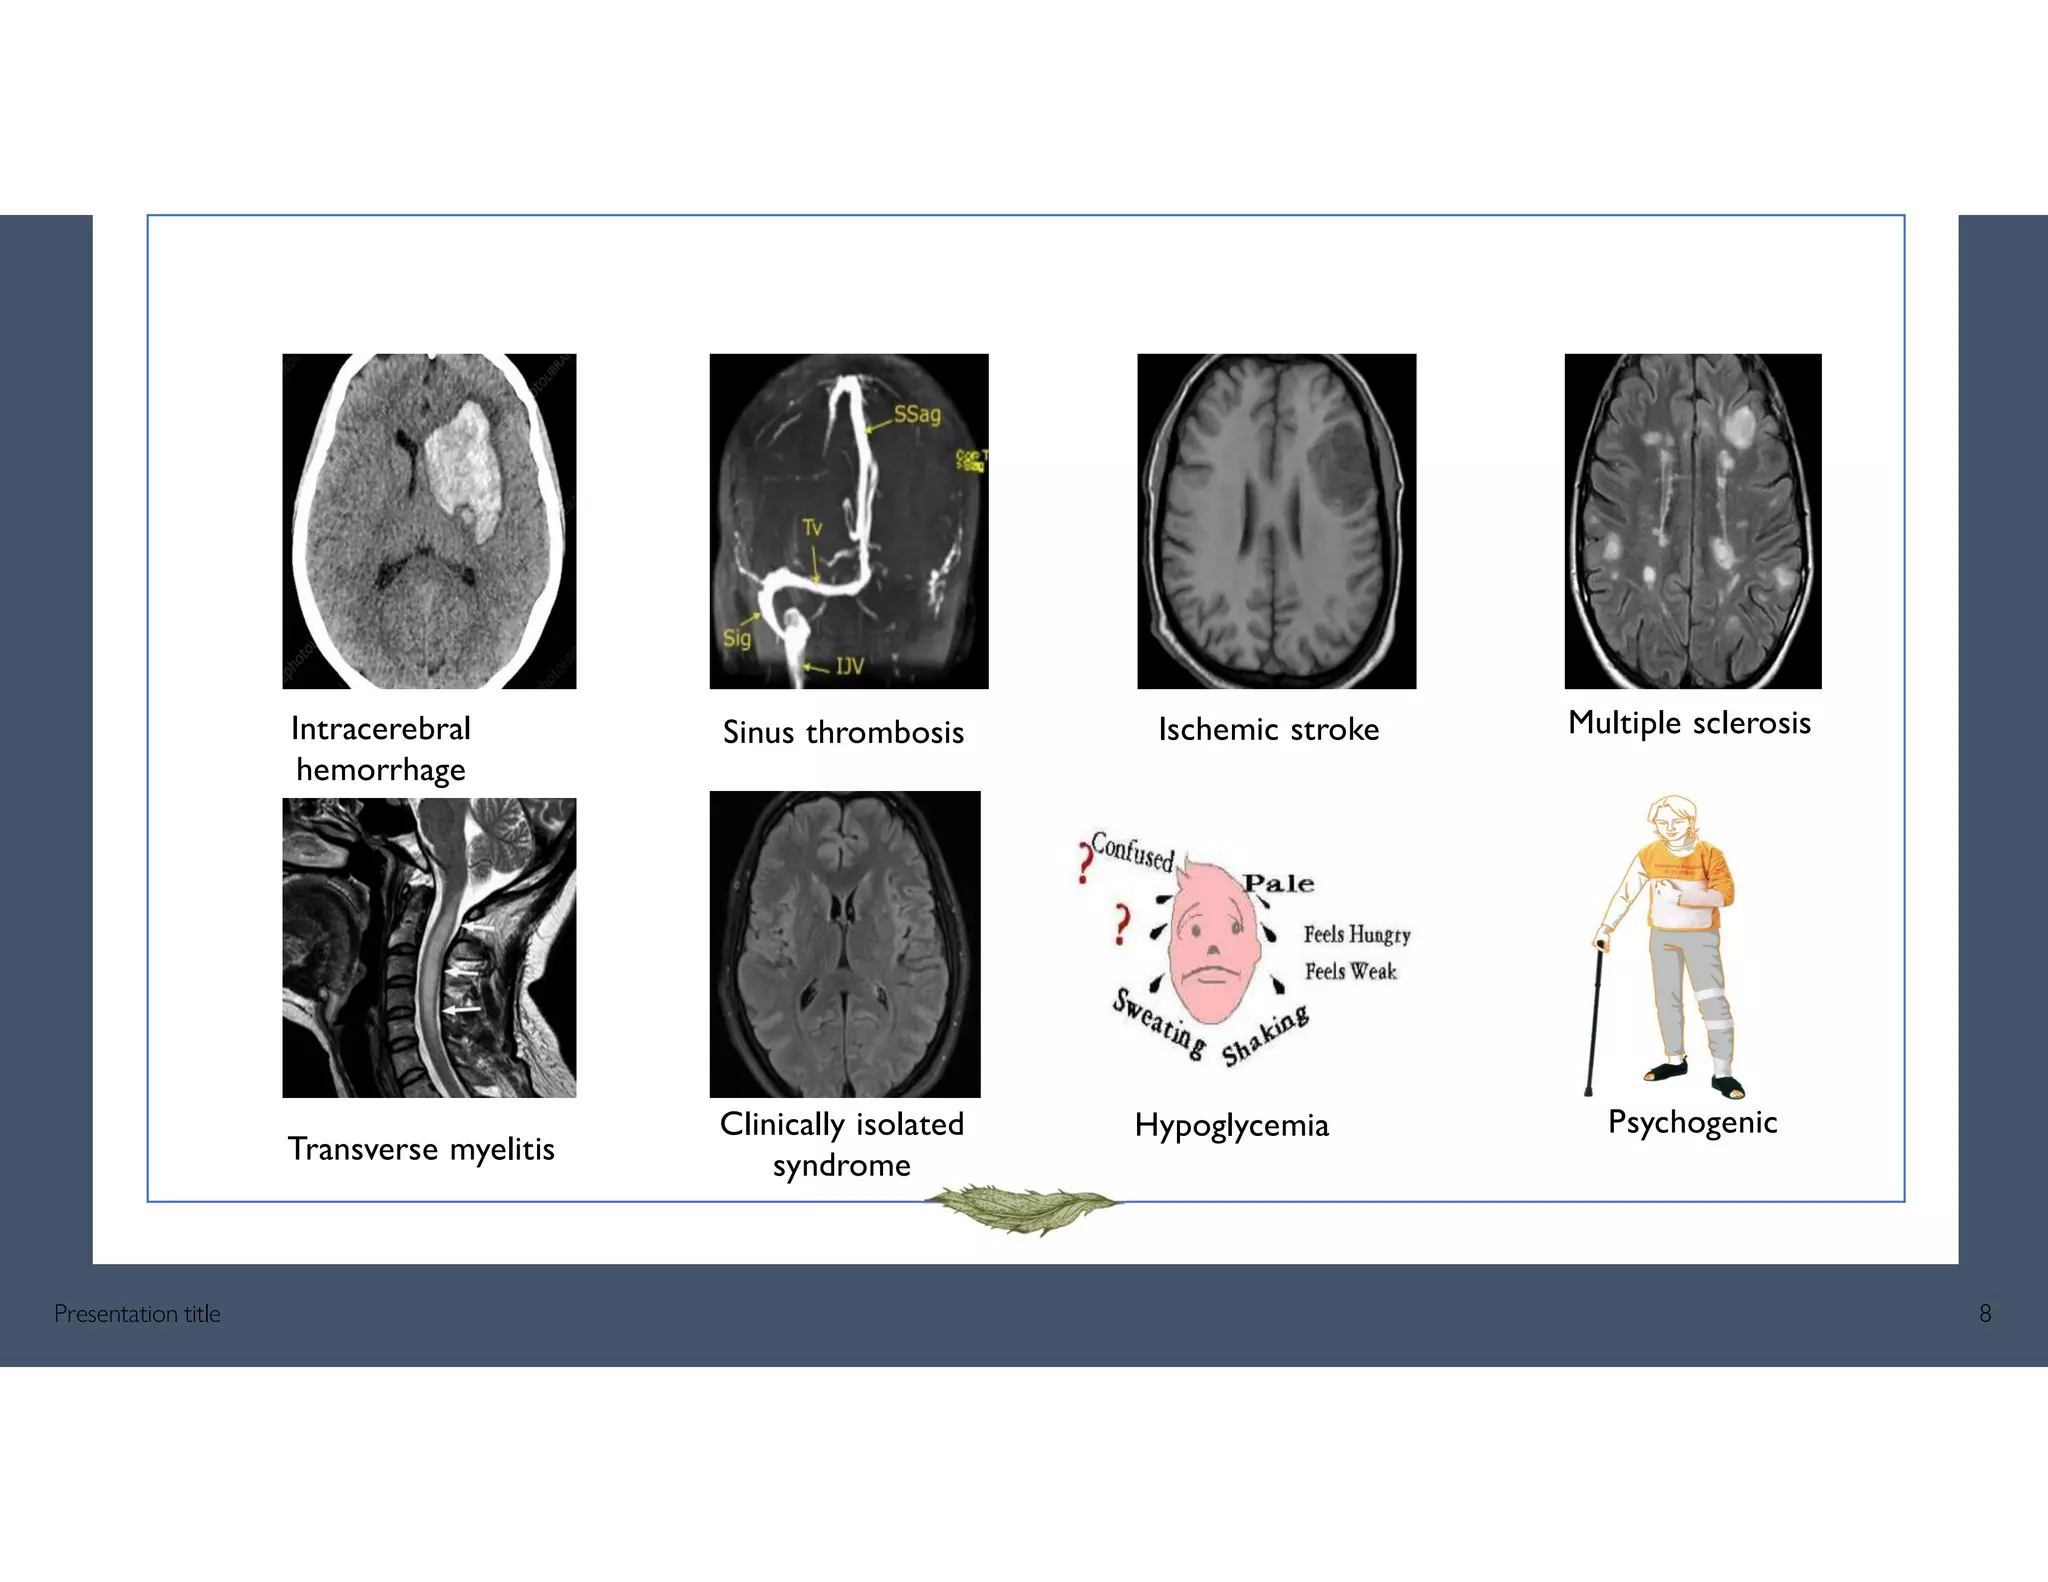

EXPECTED SCENARIOS

Intracerebral

hemorrhage

Transverse myelitis

Sinus thrombosis

Clinically isolated

syndrome

Hypoglycemia

Multiple sclerosis

Psychogenic

Presentation title 8

Ischemic stroke